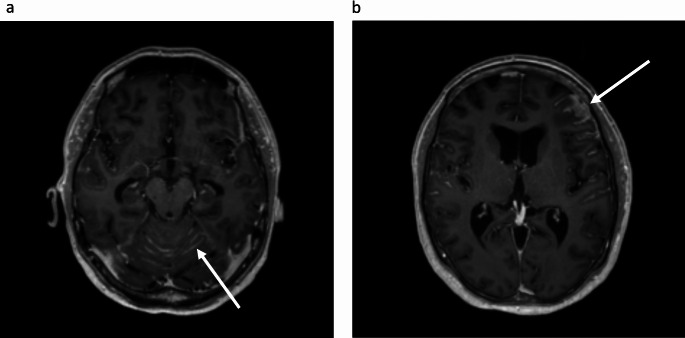

Progressive leptomeningeal metastases (LM) are associated with intractable neurological symptoms and a poor prognosis, and effective treatment options are limited. Intrathecal (IT) pemetrexed has been shown to confer clinical benefit in lung adenocarcinoma, yet our understanding of the efficacy and safety of the treatment is limited. We report a patient with a long-standing history of leptomeningeal disease due to ALK-positive adenocarcinoma of the lung, previously controlled by increased doses of lorlatinib (125 mg/day). Rapid LM progression prompted the start of IT pemetrexed, after which the patient experienced immediate clinical improvement. The case provides additional support that IT pemetrexed can offer symptomatic relief and may be considered as a treatment option in advanced LM. Furthermore, the case illustrates that an increased dose of lorlatinib may efficiently control LM in patients with ALK-rearranged NSCLC, following progression on standard lorlatinib dosage.